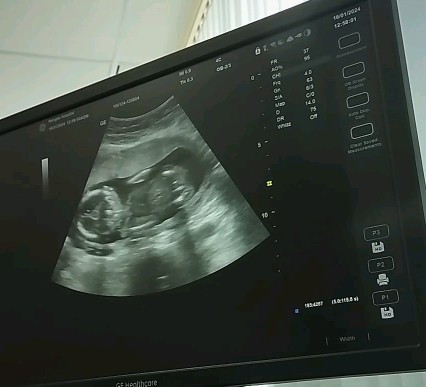

แบบนี้ลูกชายรึลูกสาวค่ะ ตื่นเต้นอยากด้ายสาวค่ะ รบกวนแม่ๆที่มีประสบการณ์หน่อยค่ะ

แม่ๆคนไหนมีประสบการณ์ทางนี้บ้าง ช่วยดูหน่อยค่ะ หญิงรึชายค่ะแบบนี้ ซาวด์ตอน20วิค ทีมมิถุนาค่ะ

อันนี้รุปทั้งตัวจะบอกอยากคะ ต้องเป็นรุปท่าก้นถึงจะชัดในการดูเพศ